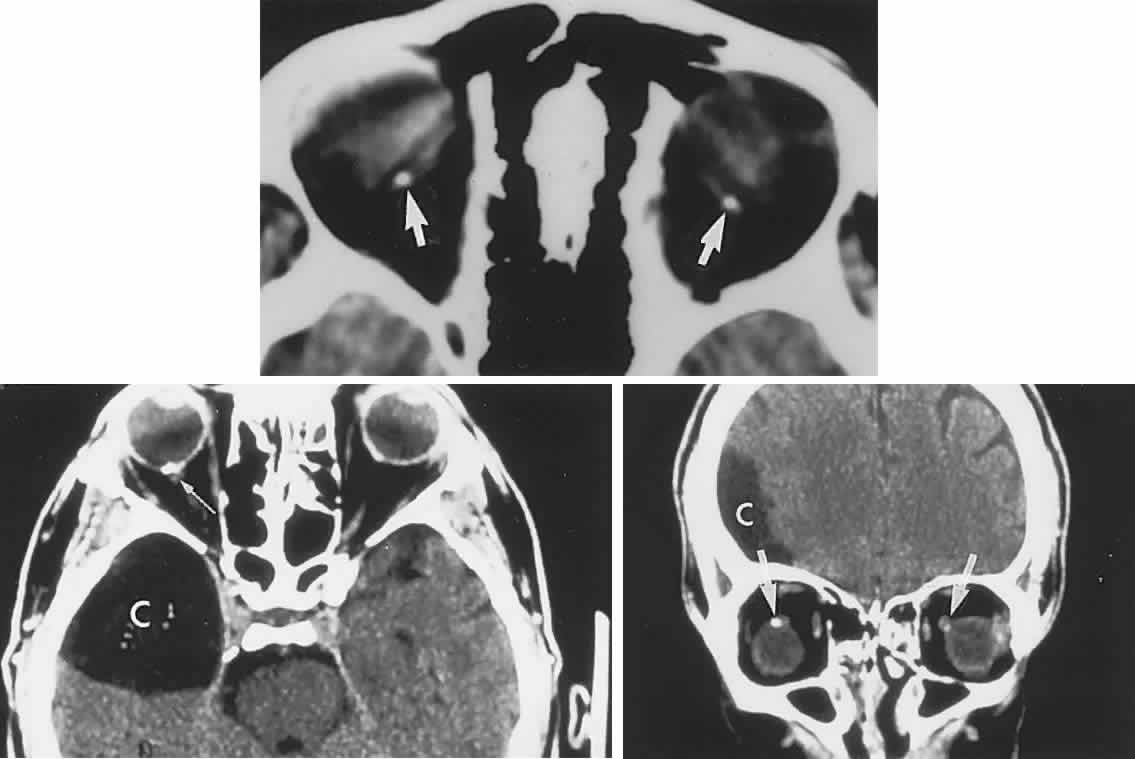

The retinal variety may be admixed in a person who suffers the more conventional attacks of migraine. It is presumed that vasospasm in the retinal circulation determines transient hypoxia, perhaps somewhat similar to the visual cortical event. On rare occasions, the fundus has been examined during typical retinal migraine episodes, and arterial constriction has been described. Wolter and Burchfield106 photographically documented such an episode and demonstrated mild “retinal edema”; vessel narrowing is also evident (Fig. 8). Fortunately, permanent complications of retinal migraine are rare. These may take the form of central retinal artery occlusion or ischemic papillopathy (see Volume 2, Chapter 16); nerve fiber bundle visual field defects may be demonstrated (Fig. 9).

Fig. 8. Retinal migraine. A. During amaurotic episode. Note the dusky appearance of the fundus, increased retinal sheen (possibly edema), and dark narrowed veins (arrows). The disc is also hyperemic. B. Fundus after episode. Compare paired arrows. (Courtesy of Dr. J. Reimer Wolter)

Fig. 9. An 18-year-old student with recurrent episodes of left retinal migraine. After a typical attack, he noted an inferior field defect. A. Fundus shows a defect in the superior arcuate nerve fiber bundle (between arrows: compare fiber layer below disc). B. Visual field defect corresponds to a retinal nerve fiber layer defect.